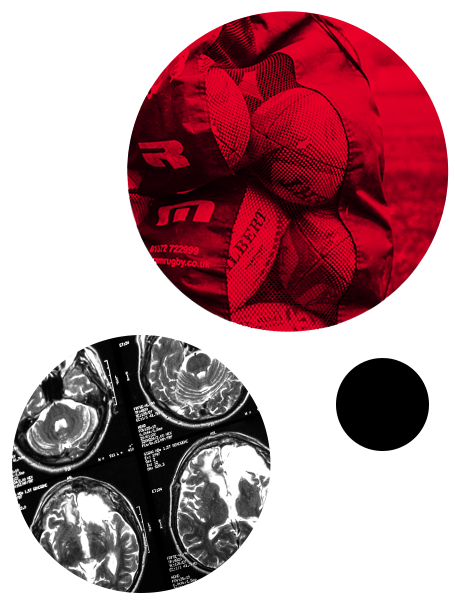

Graphics

Ben Jones Athletes fear concussions—why don’t they report them?

So we should try and reduce concussion where possible. And I'm going to talk about something else now in addition to concussion, and that's head impacts or head acceleration events as they're so eloquently named.

Now a head acceleration event is every time the head moves. And the reason this is important is recent research has shown that the more head impacts or head acceleration event an athlete is exposed to over their career, the greater their potential risk of negative long term brain health outcomes can be in the future.

So effectively we should try and reduce head acceleration events and head impacts where possible. But this does propose a challenge. How do you measure and how do you count head acceleration events or head impacts? They're effectively unseen data.

Well, until now. So there's a new technology which allows us to do this, and this is an instrumented mouth guard, and it's a gum shield with embedded sensors in.

And what this allows us to do, because the gum shield is fixed to the teeth, the teeth are fixed to the skull and, and obviously every time the school moves, we can then model what happens with the brain.

We can now precisely measure every time there's a head impact or a head acceleration event in sports. Now, some of our recent work has been validating instrument in mouth guards. So we've been working with various sporting organisations and instrument in mouth guard companies to make sure that the data that they provide are valid and accurate.

And this has then led to sports adopting these validated instrumented mouth guards. For example, World Rugby now mandate all elite players to wear instrumented mouth guards during training and matches.

The Rugby Football League also mandate elite players to wear instrumented mouth guards during matches. So the unseen data can now be seen.